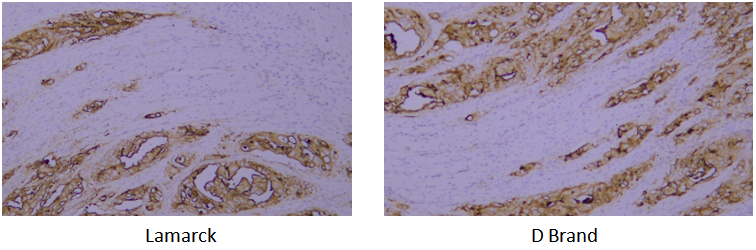

全维度质控,对标临床标准:以临床病理检测严格要求为基准建立验证体系,既对纯化后抗体的纯度、亚型、IHC 等核心指标多维度把关,保障抗体性能稳定均一;又通过与国际知名病理抗体品牌的平行对照实验,经人组织样本 IHC 结果横向比对,确保检测效果与国际顶尖水平一致且更具优越性。

Target: CD31

Tissue: human liver